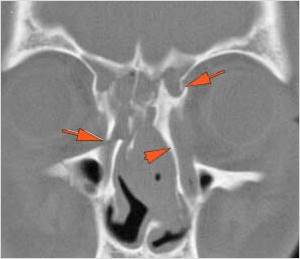

The mesial naso-orbito-ethmoid complex is fractured.  Specifically, there is bony injury of the nasal bones or the frontal process of the maxilla and the medial walls of the orbit are abnormal.

The intercanthal distance is increased.

The nasolacrimal canal is fractured.

There is injury of the ethmoid complex. Specifically, the ethmoid roof, olfactory fossa and the cribriform plate are fractured and/or significantly dehiscent.